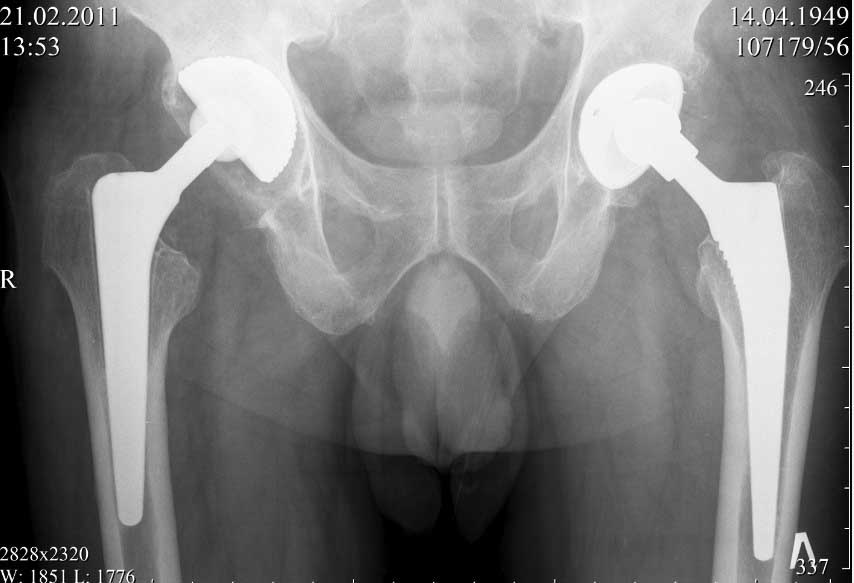

В конце 2008 года отметил боли в правой паховой области при опоре на правую ногу. На рентген снимках таза с тазобедренными суставами явных признаков нестабильности вертлужного компонента не обнаружено. В 2009 году нейрохирурги его "успешно" прооперировали на L\3-\4 связывая болевой синдром в правой паховой области с наличием грыжи указанного межпозвонкового диска. Состояние только ухудшилось, больной уже не мог долго сидеть, боль прогрессировала . Его в 2009 и 2010 годах смотрел ортопед, делались рентгенснимки, но почему то приходили к выводу что эндопротез справа стабилен. В марте 2011 года я впервые увидел его, через одну неделю после этого был прооперирован. На операции вертлужный компонент при упоре на него инструментом прокручивался во впадине и без труда был извлечен.

далее снимок у меня на приеме